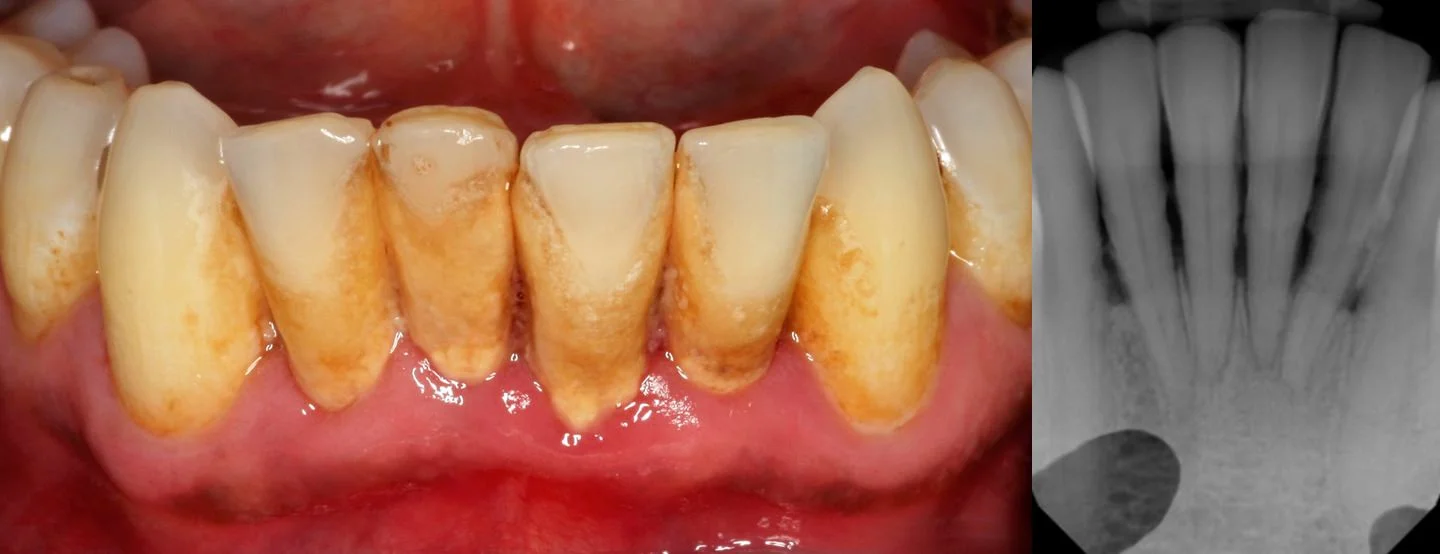

If you have certain medical conditions like diabetes you might need to have deep cleanings of your teeth done frequently.⁴ or, if you haven’t had a dental cleaning in a long time you might need a deep cleaning. Impacted teeth can also boost costs up to $600, depending upon the tooth’s location. After surveying over 600 dental practitioners, the average cleaning cost was found to be between $90 and $120.